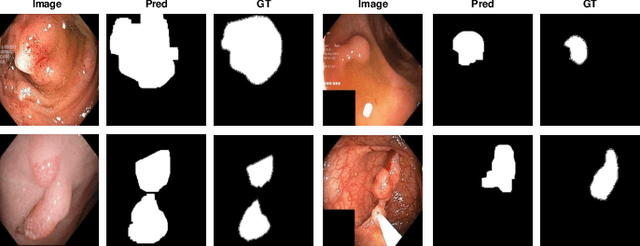

Abstract:Unsupervised anomaly detection (UAD) aims to find anomalous images by optimising a detector using a training set that contains only normal images. UAD approaches can be based on reconstruction methods, self-supervised approaches, and Imagenet pre-trained models. Reconstruction methods, which detect anomalies from image reconstruction errors, are advantageous because they do not rely on the design of problem-specific pretext tasks needed by self-supervised approaches, and on the unreliable translation of models pre-trained from non-medical datasets. However, reconstruction methods may fail because they can have low reconstruction errors even for anomalous images. In this paper, we introduce a new reconstruction-based UAD approach that addresses this low-reconstruction error issue for anomalous images. Our UAD approach, the memory-augmented multi-level cross-attentional masked autoencoder (MemMC-MAE), is a transformer-based approach, consisting of a novel memory-augmented self-attention operator for the encoder and a new multi-level cross-attention operator for the decoder. MemMC-MAE masks large parts of the input image during its reconstruction, reducing the risk that it will produce low reconstruction errors because anomalies are likely to be masked and cannot be reconstructed. However, when the anomaly is not masked, then the normal patterns stored in the encoder's memory combined with the decoder's multi-level cross-attention will constrain the accurate reconstruction of the anomaly. We show that our method achieves SOTA anomaly detection and localisation on colonoscopy and Covid-19 Chest X-ray datasets.